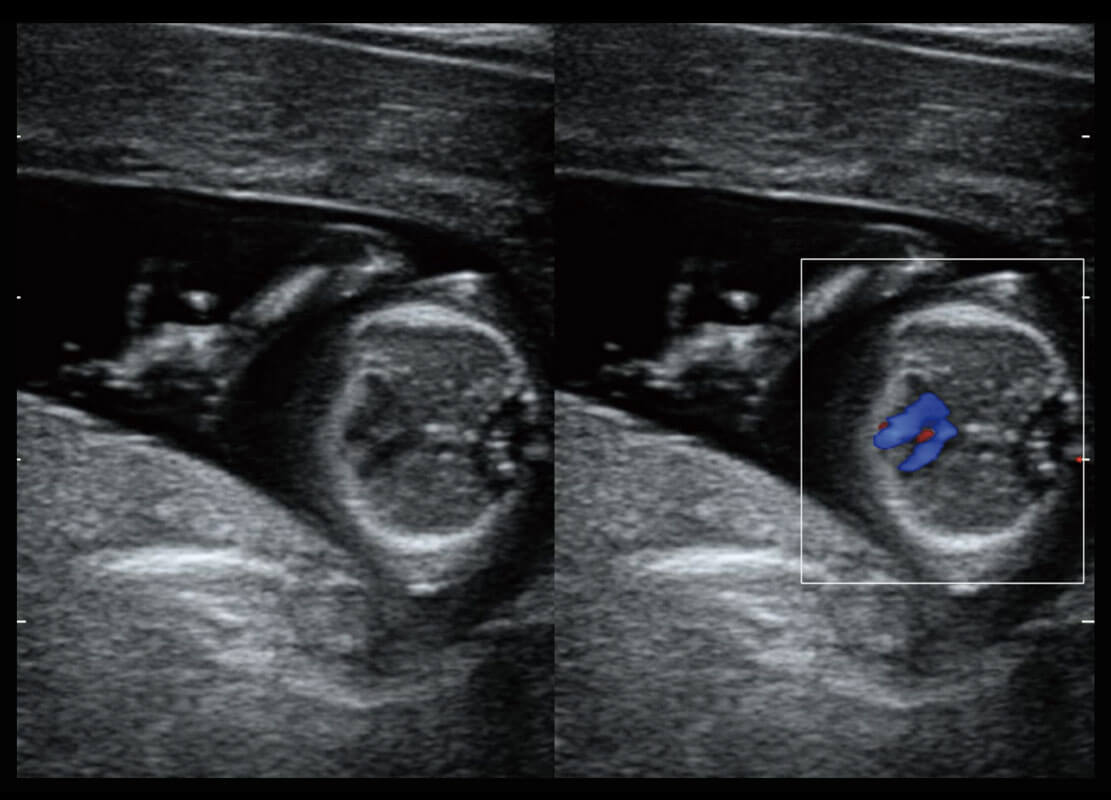

早孕筛查

P60在胎儿早孕期超声筛查中为您带来优异的图像质量。

• 早孕-胎心

• 胎儿体循环